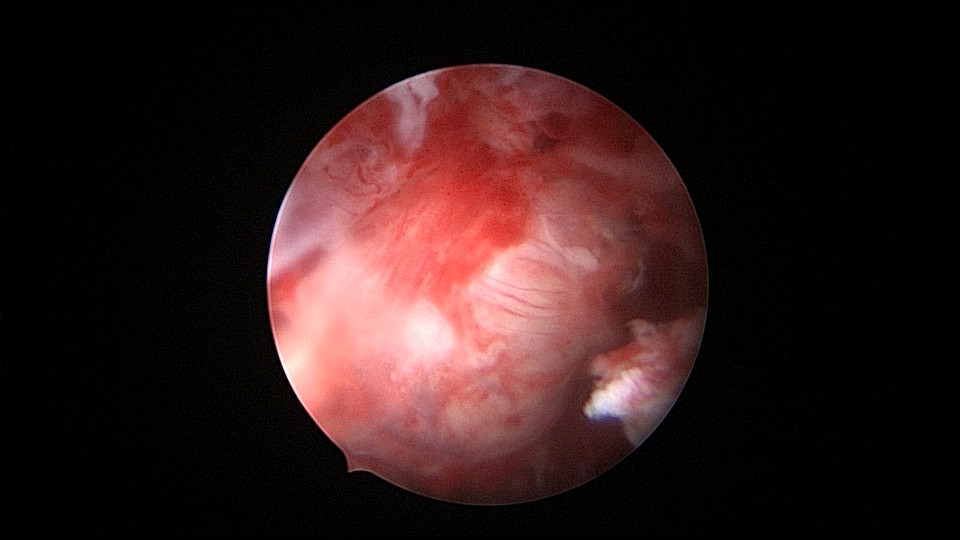

患者55岁,G4P1,顺产1次。安环16年,绝经5年,外院取环失败。子宫前位,宫颈萎缩,宫腔下段左后壁见假道,假道内见肌瘤结节突出,爱母环位置正常,宫腔左侧壁及前壁见占位质脆组织,表面有异常粗大血管。异物钳顺利取出节育环,占位组织病检为内膜样癌。取环造成的假道让病人因祸得福,提前发现了子宫内膜样癌,得以及时手术治疗。